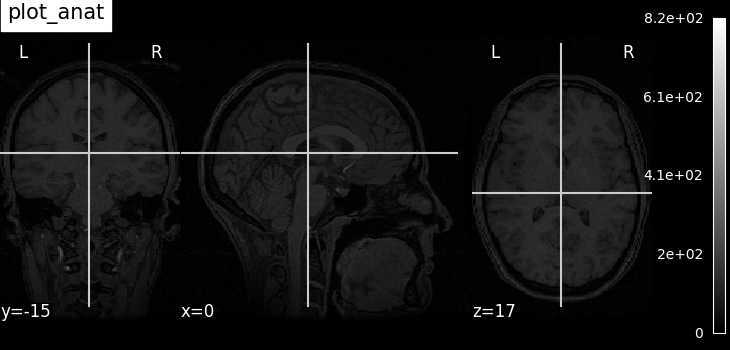

Plotting anatomical images: plot_anat¶

Visualizing anatomical image of haxby dataset

plotting.plot_anat(haxby_anat_filename, title="plot_anat")

<nilearn.plotting.displays._slicers.OrthoSlicer object at 0x7f36fa8119a0>